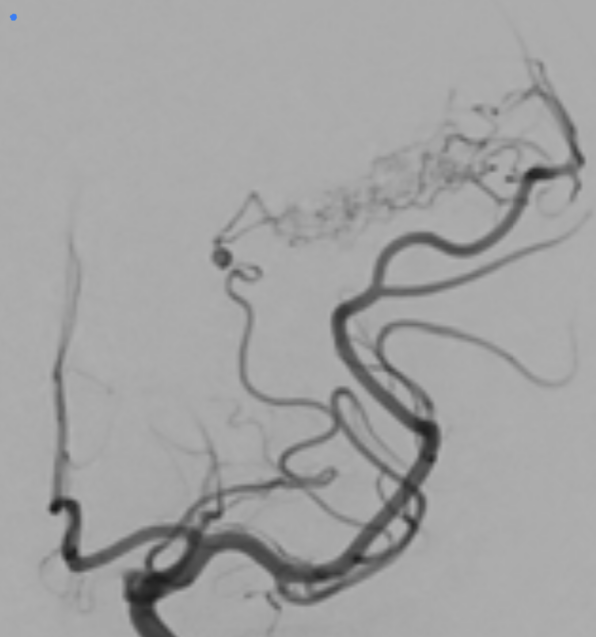

AVM - architecture

AVM - topography and vessels involved

protocol